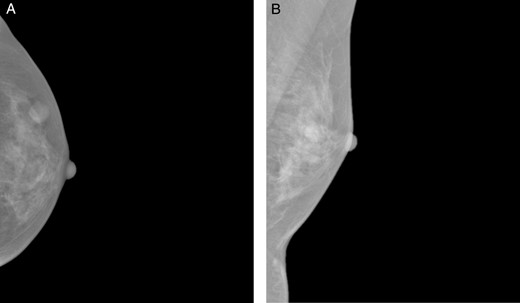

A 37-year-old Chinese female presented with a lump in the left breast that was slowly growing over a duration of 8 years. Aside from a history of amenoblastoma of the jaw which was excised 3 years ago, she has no significant medical history. On physical examination a firm 1-cm nodule was palpable at the 3 o'clock position of the left breast. Mammography showed a well-circumscribed opacity in the left breast (Fig. 1) and ultrasound revealed an ovoid 1.5 × 1.5 × 0.9 cm heterogeneous solid hypoechoic nodule with well-defined, regular margins (Fig. 2). The lesion contained some anechoic areas suggestive of cystic clefts which are consistent with sonographic features of a phyllodes tumour [1, 2].

Craniocaudal (A) and mediolateral oblique (B) mammographic views demonstrating a well-circumscribed opacity in the central outer quadrant of the left breast.

On mammography, most schwannomas appear as well-circumscribed opacities. In certain cases, they may be mammographically occult or may present as ill-defined soft tissue densities [3]. Sonographically, they are generally described as well-defined hypoechoic lesions. Other features suggestive of a schwannoma on ultrasound include target sign (hyperechoic centre and hypoechoic periphery), posterior acoustic enhancement and peripheral nerve continuity. However, these features may also represent other peripheral nerve sheath tumours like neurofibromas [8]. The mass in our patient had cystic areas which were also reported by Lee [5] and Uchida [3].